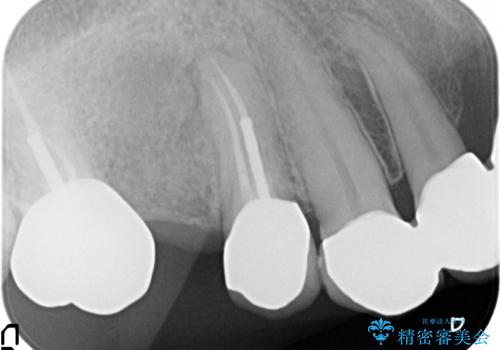

- アメリカの歯科医院にて治療途中の歯の仮歯が割れてしまったので診て欲しいといらっしゃった方の症例です。

しばらくアメリカに戻れそうにないため、当院での治療を希望。土台の築造まで処置は終わっているとのことだったのでオールセラミッククラウンによる補綴のみを行いました。

※遠心の欠損部はアメリカにてインプラント予定とのこと。